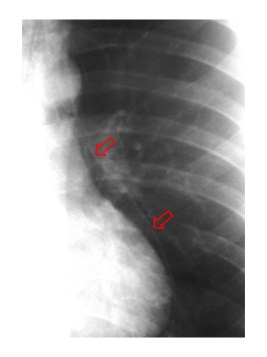

Radiografía AP de tórax en un paciente con traumatismo torácico. A la derecha las flechas marcan el signo de la V de Naclerio.

Signo de neumomediastino en la radiografía de frente de tórax. Corresponde a la presencia de aire mediatínico que ocupa la parte inferolateral del mediastino. El brazo medial de la V lo forma el aire que delimita la porción inferior del margen mediastínico izquierdo, mientras que el brazo lateral de la Vestá producido por el aire entre la pleura parietal y el hemidiafragma izquierdo.

En las fotografías vemos el signo en un paciente con traumatismo torácico que también presenta enfisema subcutáneo extenso (marcado en amarillo) y una contusión pulmonar en el lado izquierdo (flechas azules).